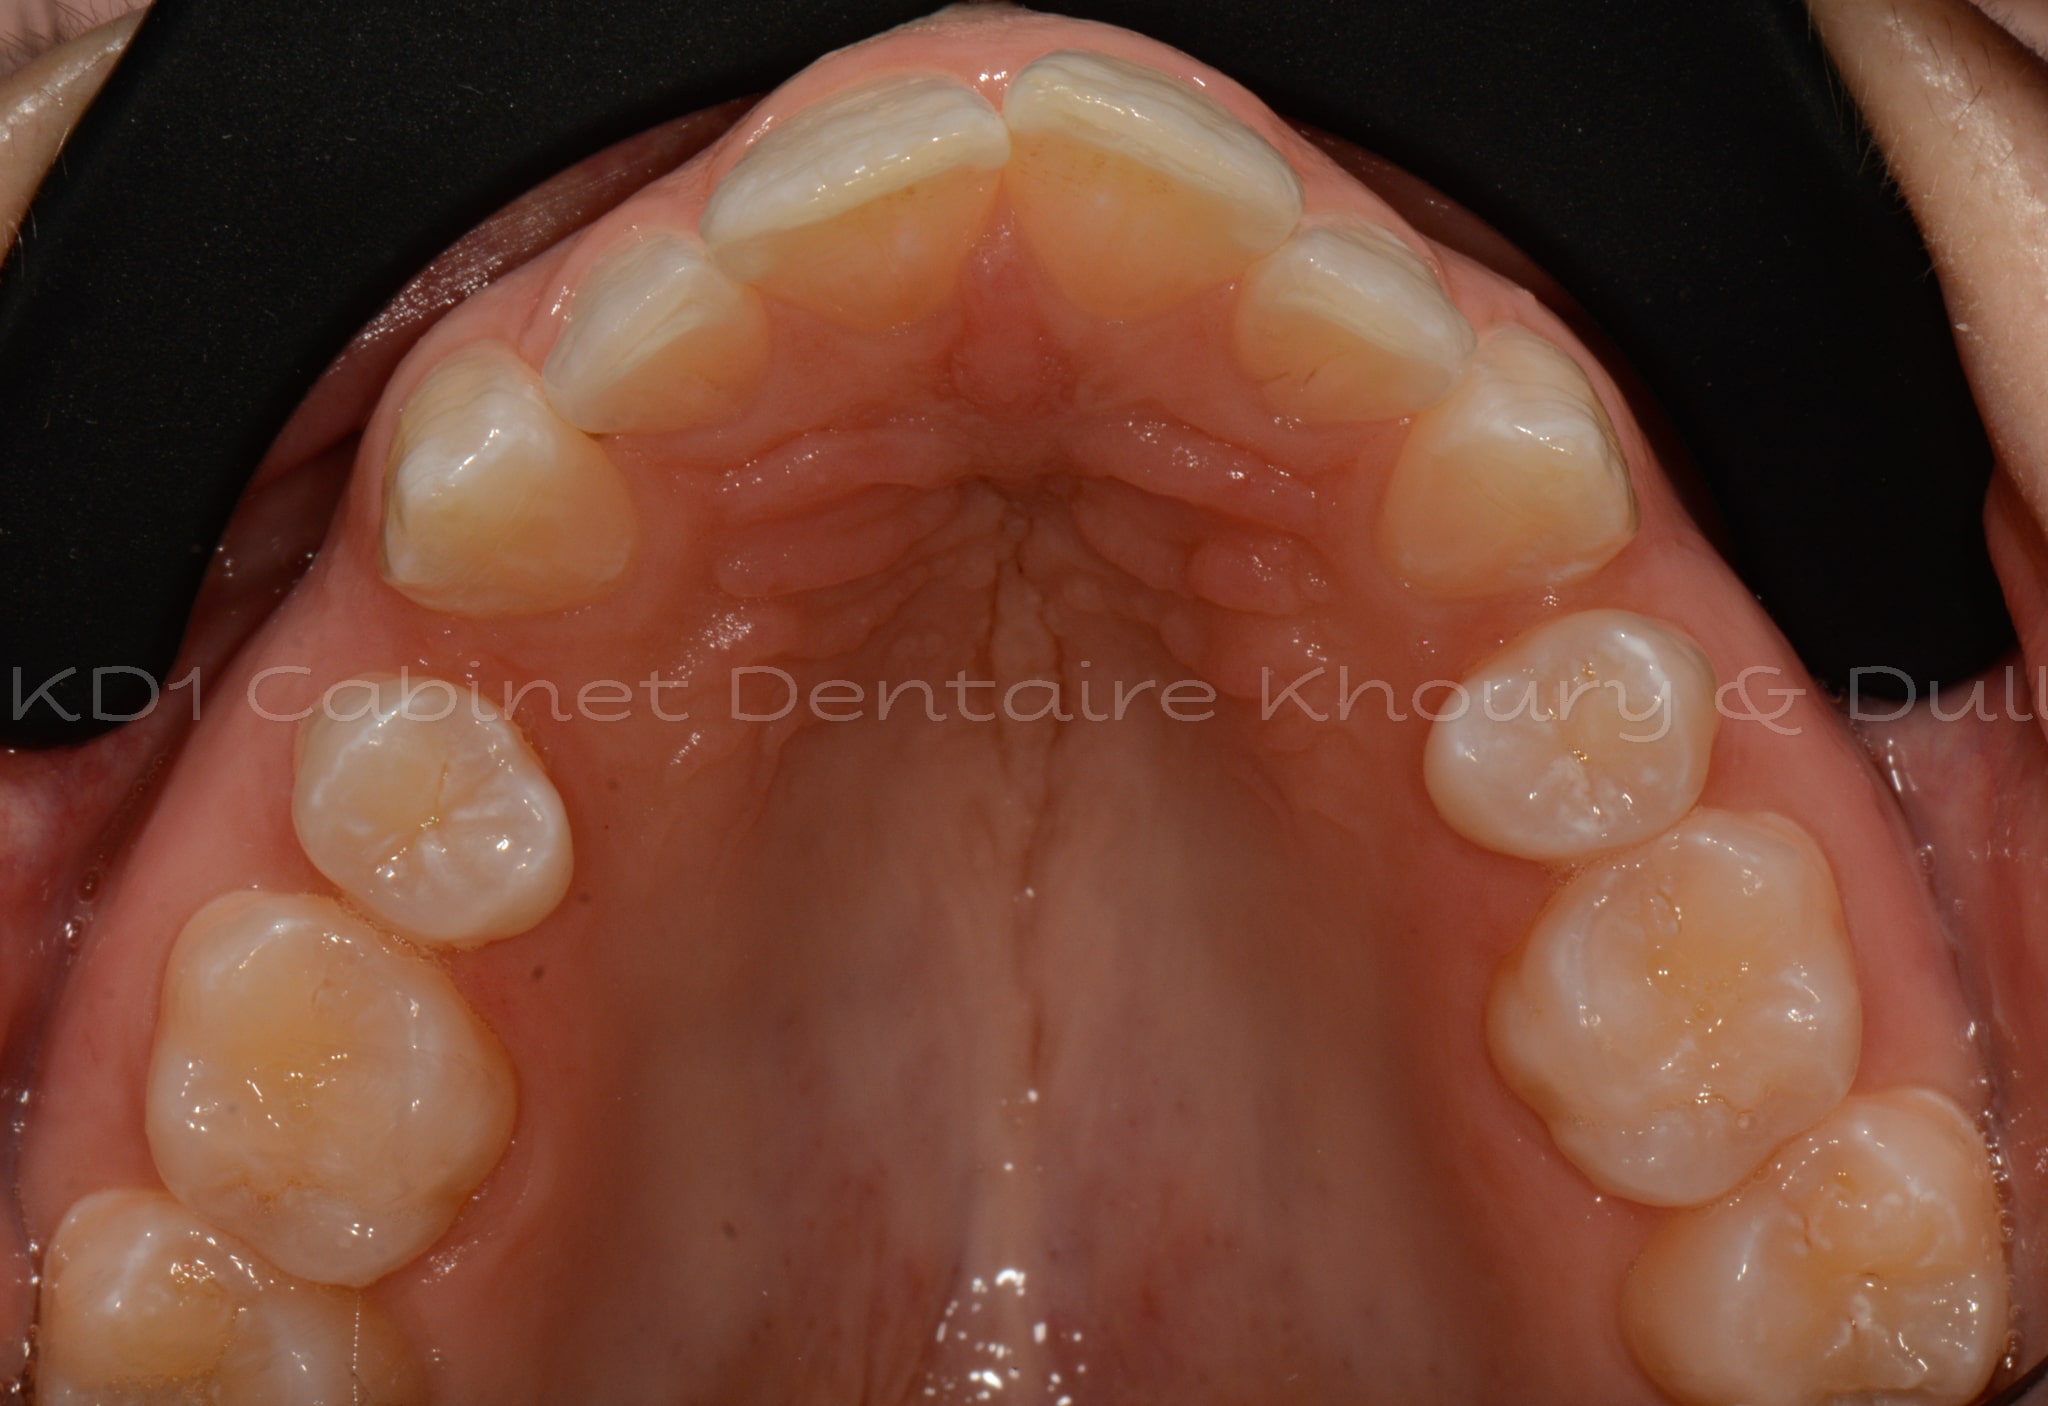

Cas #1 – Traitement avec des bagues, deuxièmes prémolaires et dent de sagesse supérieures ectopiques.